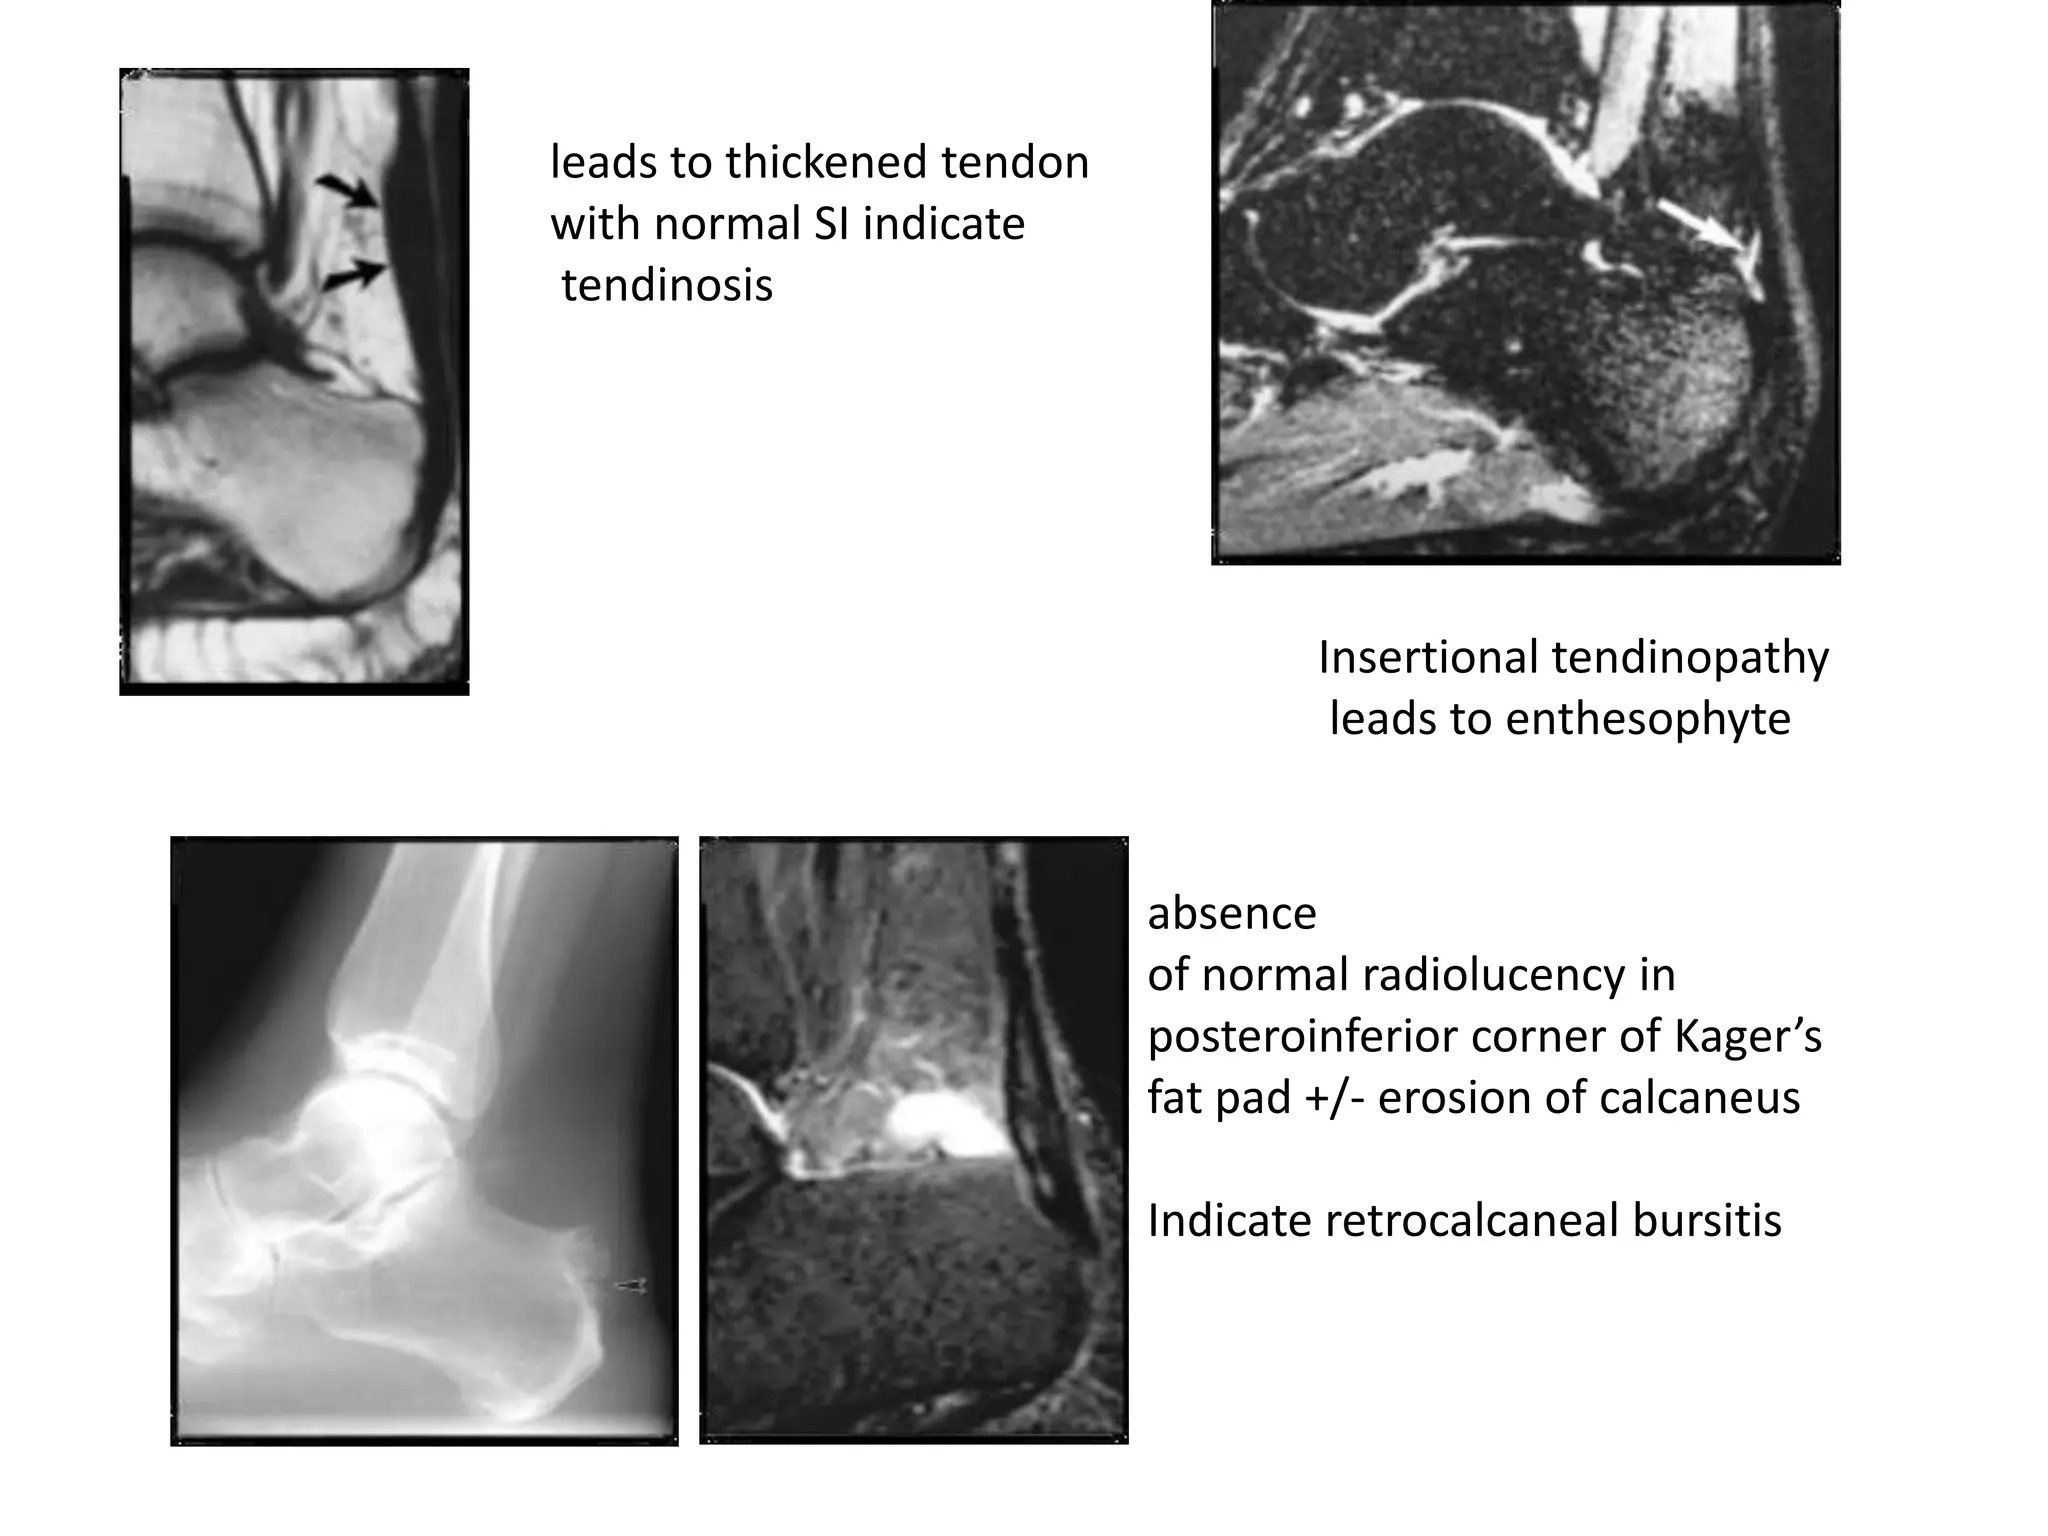

leads to thickened tendon

with normal SI indicate

tendinosis

Insertional tendinopathy

leads to enthesophyte

absence

of normal radiolucency in

posteroinferior corner of Kager’s

fat pad +/- erosion of calcaneus

Indicate retrocalcaneal bursitis